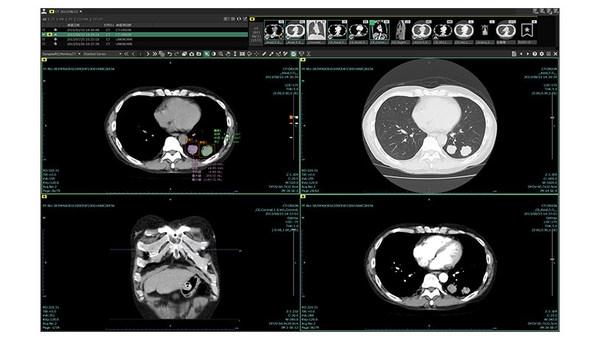

3. 新一代影像诊断工作站 “SYNAPSE SAI viewer V1.3”

该产品是一款利用人工智能(AI)技术开发的辅助医生进行影像诊断工作的平台。利用“肺结节筛查功能”和“肺结节智能分析功能”,前者从胸部CT图像中自动识别并标记多种肺结节病灶,后者提供多维度的分析肺结节性状功能,同时可以生成智能治疗意见和结构化报告,减轻医生的读片工作量,提高影像诊断效率。

【评审团评价】

通过使用AI技术分析胸部CT图像,从而实现疾病的早发现、早治疗,给医生和患者都带来了很大的好处。而除了辅助检测,该软件的数值和图表可视化、绘图工具等功能还能辅助图像诊断的工作流程。

富士胶片新一代影像诊断工作站 “SYNAPSE SAI viewer V1.3”入围“GOOD DESIGN BEST 100”